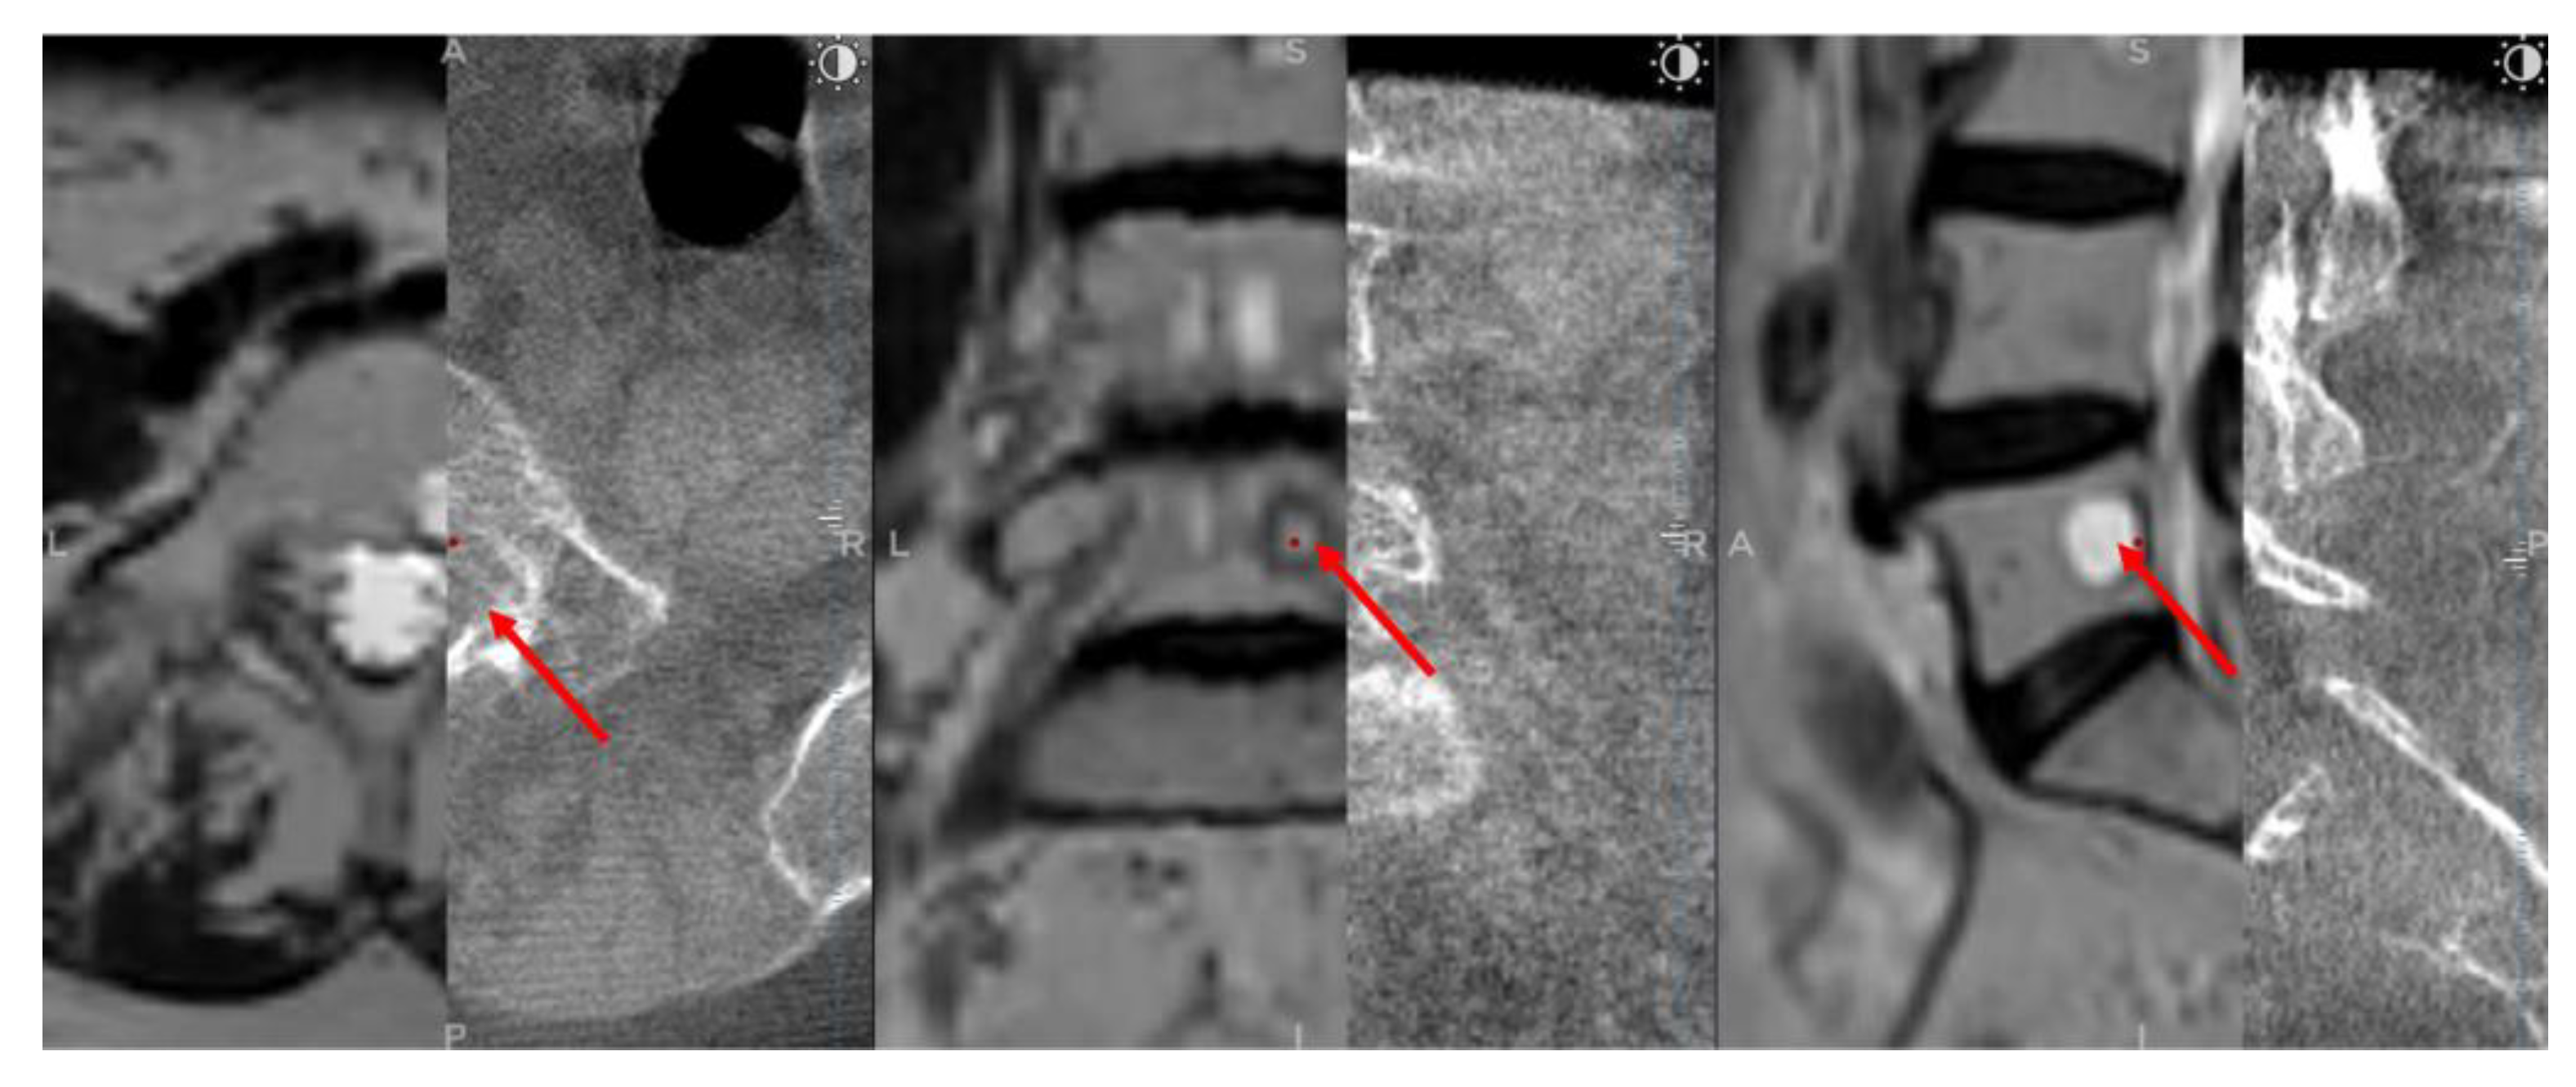

To validate that CT images were improved through merging with MRI images, the tumor dimensions were measured separately on axial, sagittal, and coronal planes in cases where the tumor was found in both modalities. While MRI scans revealed tumors in all 17 patients, CT scans revealed tumors in only 8 cases, implying that some tumors were not visible on CT (Figure 4). As a result, we could only compare tumor dimensions in these 8 cases. GraphPad Prism 9 software was used to perform statistical analysis with a significance level set at p ≤ 0.05. Normality was checked for all data distributions, and a student t-test was employed depending on the results. The Pearson correlation coefficient was also calculated to examine the correlation between data sets.

Figure 4. O-arm and MRI fused images, with A) axial view, B) coronal view, and C) sagittal view. The left half of each view displays the O-arm scan. The right half displays the MRI scan. Red arrows indicate the tumors, and yellow arrows show where the tumor should be visible.